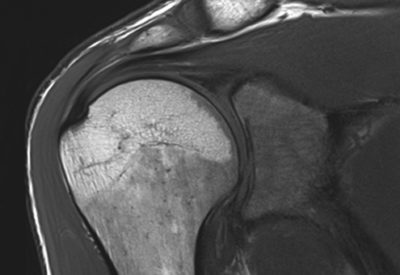

Hochwertige MRT-Untersuchung für maximale Diagnosesicherheit

Dann sind Sie bei uns richtig! Wir bieten Ihnen ein erfahrenes und spezialisiertes Ärzteteam, das MRT-Untersuchungen mit moderner Gerätetechnik durchführt. Unsere MRT-Untersuchungen sind optimiert und liefern hochauflösende Bilder, die eine maximale Diagnosesicherheit bieten.

Hochwertige MRT-Untersuchung für maximale Diagnosesicherheit

Dann sind Sie bei uns richtig! Wir bieten Ihnen ein erfahrenes und spezialisiertes Ärzteteam, das MRT-Untersuchungen mit moderner Gerätetechnik durchführt. Unsere MRT-Untersuchungen sind optimiert und liefern hochauflösende Bilder, die eine maximale Diagnosesicherheit bieten.